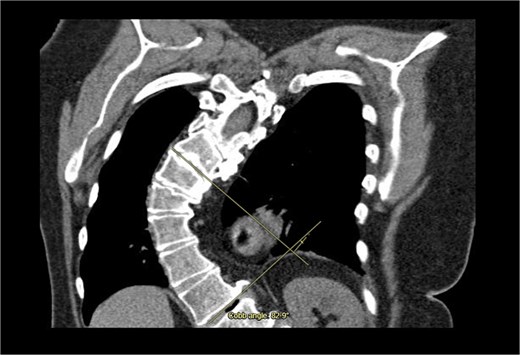

A 71-year-old female was referred to the heart team for elective minimally invasive MVR and septal myectomy. She presented with severe mitral regurgitation and hypertrophic obstructive cardiomyopathy (HOCM). Her body surface area was 1.51 m2, and BMI was 29.42. Critically, her scoliosis had a Cobb angle of 80° (Fig. 1), qualifying as extremely severe.

Coronal computed tomography (CT) with measurement of the cobb angle.